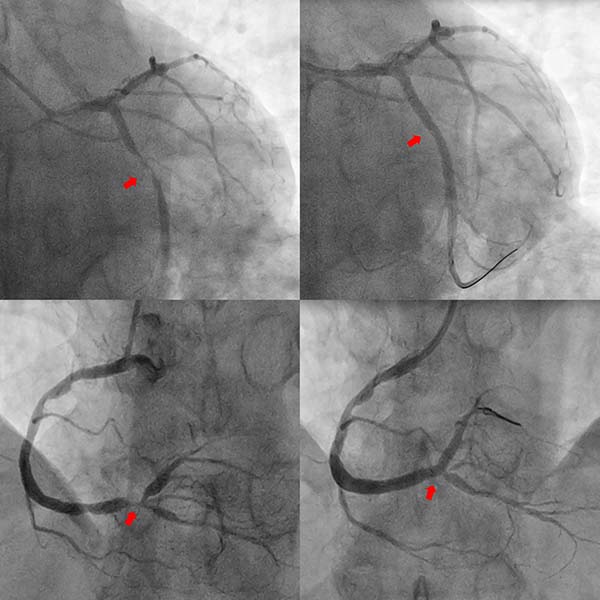

案例2

2025年6月23日凌晨,兰先生因突发胸痛由120急救车送至清华大学附属垂杨柳医院急诊,心电图提示下壁导联ST段抬高,拟诊断为急性下壁ST段抬高型心肌梗死。然而兰先生2年前被诊断为食管恶性肿瘤,手术后经历多轮次放化疗,发病2天前刚刚结束最后1次化疗。消化道肿瘤及放化疗增加了消化道出血风险。然而时间就是心肌,面对缺血和出血同样高危的患者,心内科胸痛绿色通道团队讨论后决定优先考虑开通梗死相关血管,自患者进入清华大学附属垂杨柳医院大门仅用时68分钟即开通患者右冠脉闭塞病变,因患者急诊术中冠脉血栓负荷重,行血栓抽吸及球囊扩张后,经强化抗栓治疗1周,择期于右冠脉病变处置入新型药物涂层支架。术后一个月,将双抗改为单抗,降低了消化道出血风险。

案例3

尹先生于2025年9月7日因结肠癌就诊于清华大学附属垂杨柳医院普外科,拟行结肠癌根治术。之前5年前曾因心绞痛于清华大学附属垂杨柳医院心内科行冠脉支架置入术。术前评估完善了冠脉CTA检查,结果提示:冠脉多发重度狭窄。遂由普外科转入心内科行冠脉造影提示患者回旋支、右冠脉重度狭窄,同期分别置入新型药物涂层支架,从心内科出院后1个月在普外科病房完成结肠癌手术。